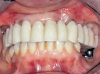

Fig 20. Frontal view at 20-year follow-up.

Figure 20

In 2020, the patient presented to the NYUCD Periodontology and Implant Dentistry Clinic. A clinical examination and radiographic evaluation showed that the patient's maxillary arch still exhibited good peri-implant soft-tissue health and stable marginal bone level with slight bone loss on implants Nos. 2, 6, 8, and 11 (Figure 18 through Figure 20). The maxillary prosthesis showed adequate stability with a slight chipped suprastructure on the porcelain on the right side. The patient was advised to substitute the implant-supported, screw-retained hybrid acrylic complete denture in the maxilla with a fixed, implant-supported, screw-retained prosthesis, which she declined due to financial considerations.